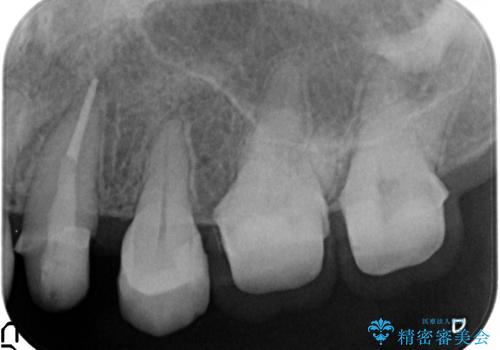

終了時

左:虫歯を除去したところ。遠心が歯ぐきより深い状態です。中:そのままかぶせようとすると、遠心が歯ぐきが腫れやすい状態です。右:エクストリュージョンをしたことで、遠心の歯ぐきの腫れが収まっていることがわかります。

エクストリュージョンをしたことで、いくら歯磨きを頑張ってもどうしても腫れてしまう歯肉に対して、歯周囲組織の位置関係を変えることで根本的に解決しました。

今回は、単独1歯のエクストリュージョンを、マウスピースを使って、ご自身でゴムをかけていただき行ったのがポイントです。

歯の変色もあるため、最終的にはクラウンとしました。